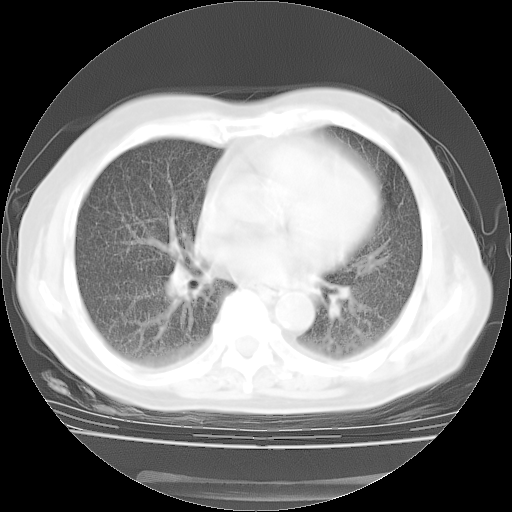

4月14日肺部CT

23.JPG

24.JPG

25.JPG

26.JPG

肺部CT平扫未见异常。